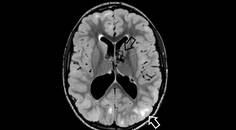

In addition to muscular abnormalities, numerous other systems are involved in LOPD. Cerebrovascular involvement including stroke, aneurysm, and hemorrhage has been described and, although it is not fully understood, may be related to glycogen deposition in the smooth muscle component of cerebral arteries.12 A study of over 200 individuals found cerebral aneurysmal rupture resulted in 3% of deaths, although the study population included people with atypical forms of infantile Pompe disease.3 Small fiber neuropathy has been described, and a study reported neuropathic involvement in 50% of the people who reported pain and discomfort or temperature alterations.9